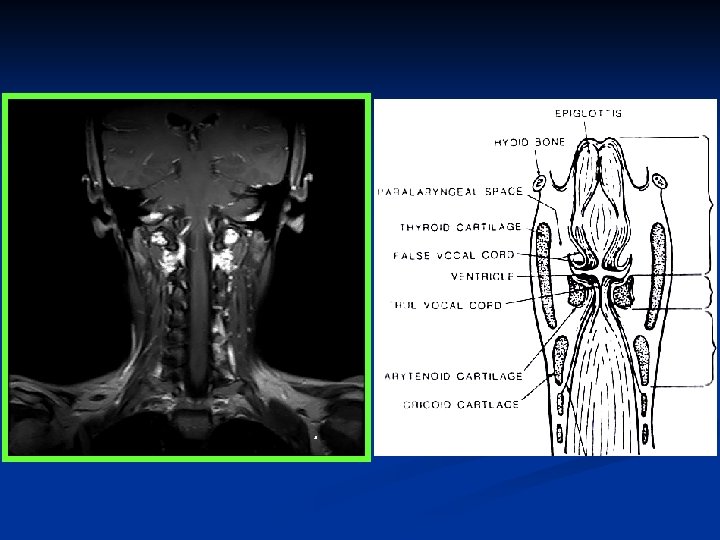

Larynx Composed of a mucosal surface and a supporting cartilaginous skeleton. n Mucosal surface: epiglottis, true and false cords, aryepiglottic folds, and pyriform sinuses n Skeleton: Hyoid cartilage, thyroid cartilage, cricoid cartilage, and arytenoid cartilage n Between mucosa and skeleton: paraglottic and preepiglottic spaces (loose areolar tissues, lymphatics, muscular structures) n

Skeleton n n Hyoid Bone - attachment to epiglottis and strap muscles. Thyroid Cartilage - anterior attachment of vocal folds. Posterior articulation with cricoid cartilage. Cricoid Cartilage - complete ring. Articulates with thyroid and arytenoid cartilages. Arytenoids - two cartilages which glide along the posterior cricoid and attach to posterior ends of vocal folds.

Skeleton Hyoid Bone n Thyroid Cartilage n Cricoid Cartilage n Arytenoids n

Larynx

Larynx n Divisions -- Supraglottis -- Glottis -- Subglottis -- Paraglottic (Parapharyngeal) space -- Preepiglottic space

Supraglottis n n n Usually covered with respiratory epithelium containing mucous glands. Epiglottis - leaf-shaped mucosal-covered cartilage, which projects over larynx. Aryepiglottic folds (AE folds) - extend from the lateral epiglottis to the arytenoids. False vocal cords - mucosal folds superior to the true glottis. Separated from true vocal folds by the ventricle. Ventricle - mucosal-lined sac, variable in size which separates the supraglottis from the glottis.

Supraglottis Suprahyoid epiglottis (both lingual and laryngeal aspect) n Infrahyoid epiglottis n False vocal cords (ventricular bands) n Aryepiglottic folds (laryngeal aspects) n Arytenoid cartilages n Ventricles n

Glottis n The true vocal folds attach to the thyroid cartilage at the anterior commissure. The posterior commissure is mobile, as the vocal folds attach to the arytenoids. Motion of the arytenoids effects abduction or adduction of the larynx. The bulk of the vocal fold is made up of muscle covered by mucosa. The free edge is characterized by stratified squamous epithelium. The vocal folds abduct for inspiration and adduct for phonation, cough, and valsalva.

Glottis n True vocal cords, including anterior and posterior commissures